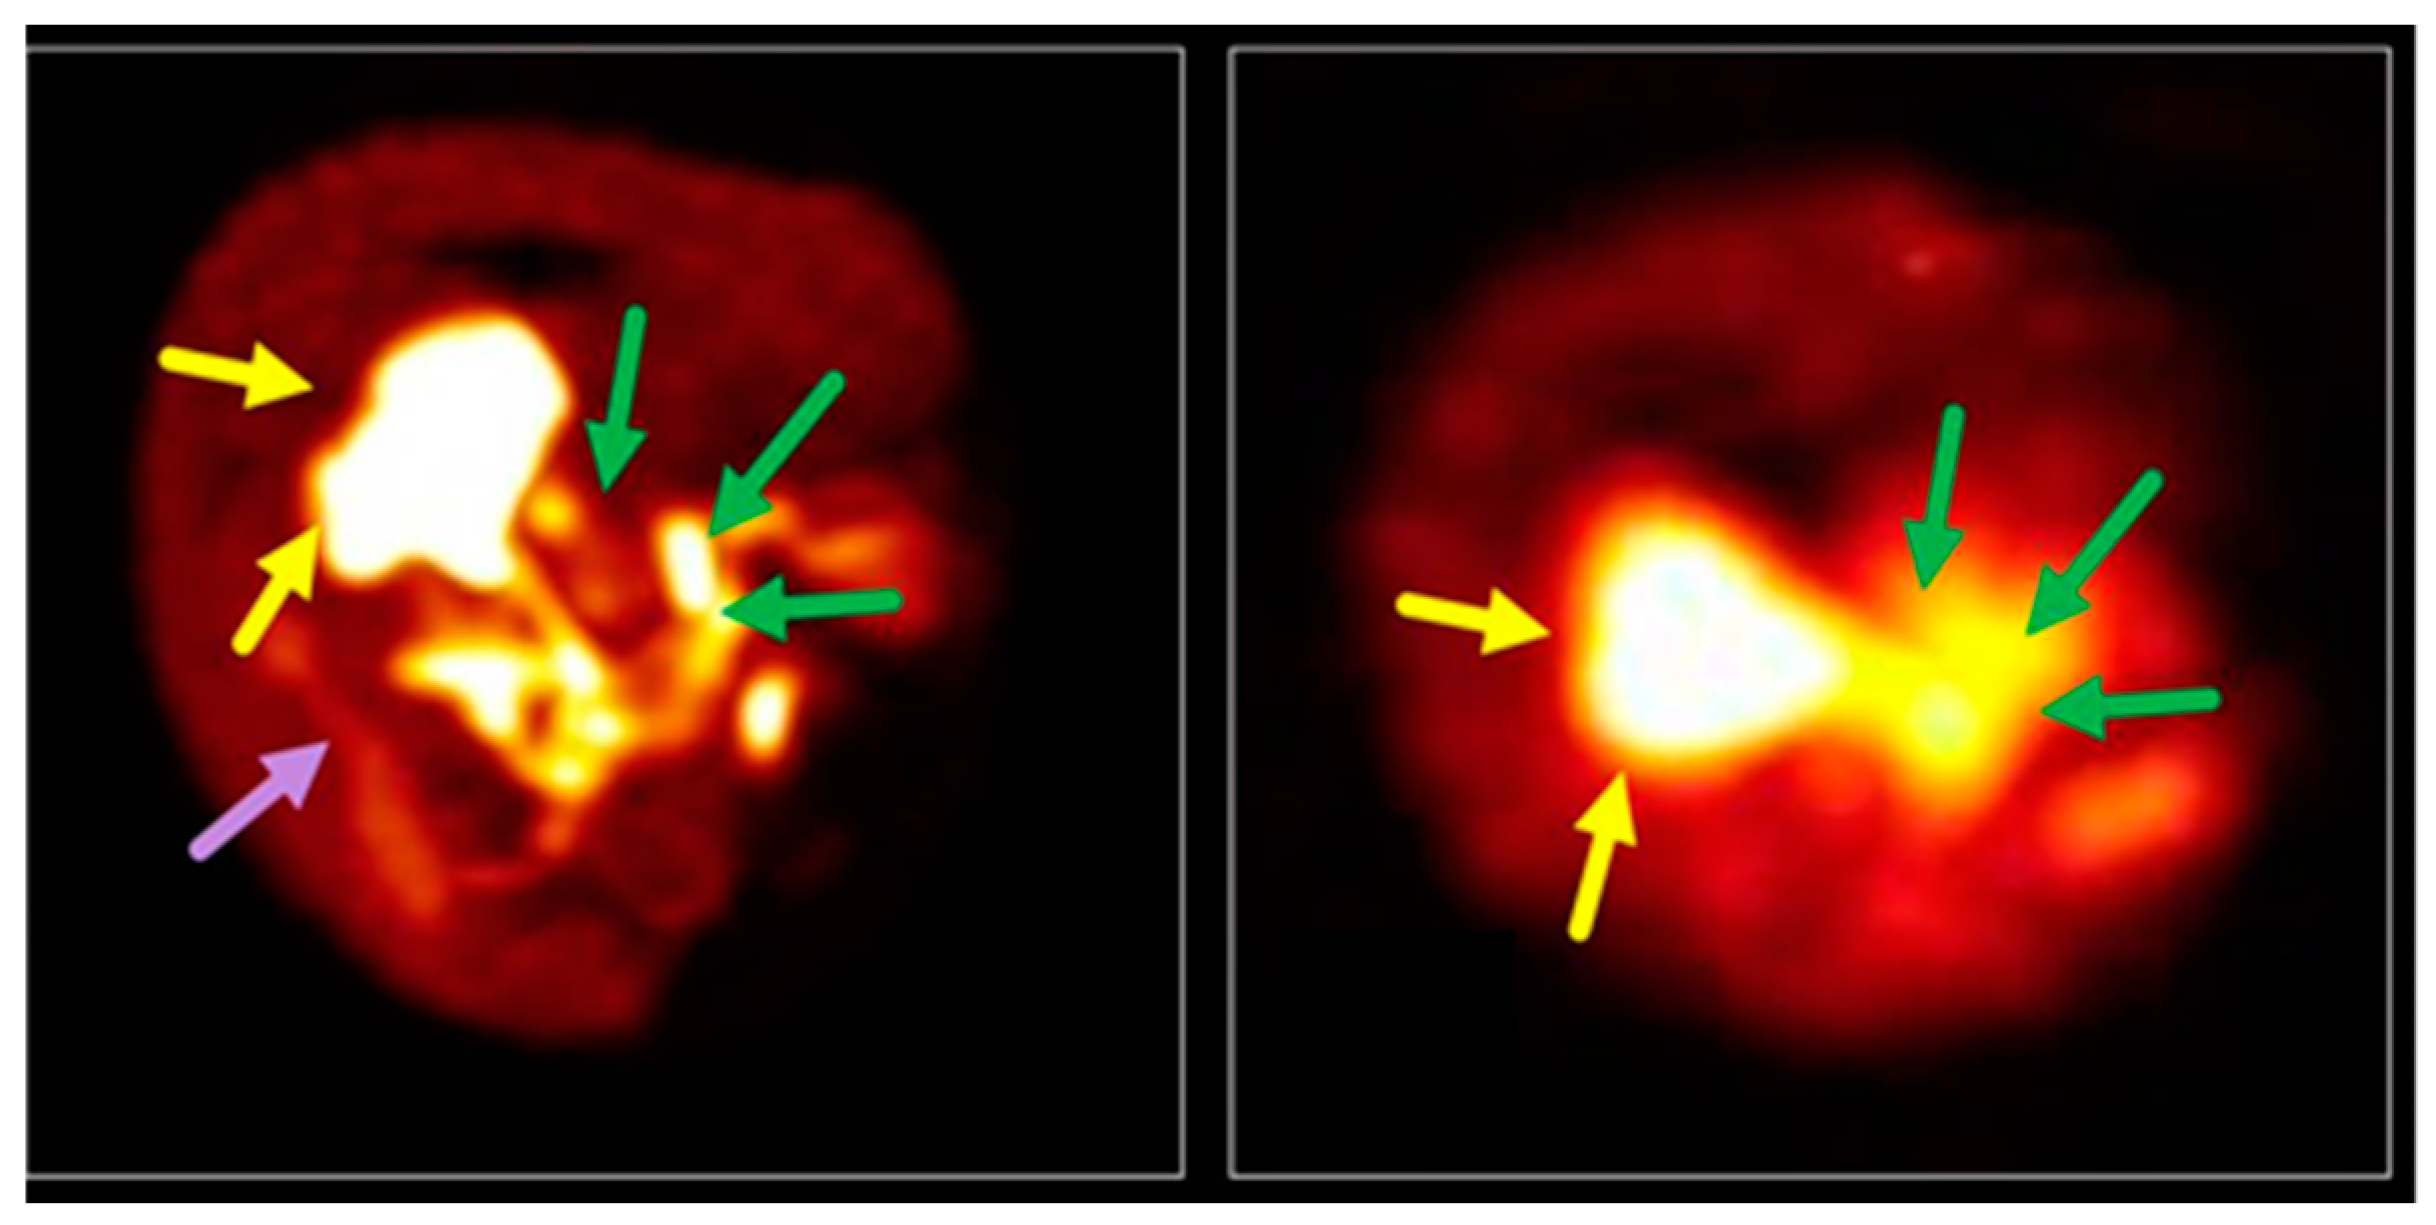

- Cheung, T.T.; Ho, C.L.; Lo, C.M.; Chen, S.; Chan, S.C.; Chok, K.S.H.; Fung, J.Y.; Chan, A.C.Y.; Sharr, W.; Yau, T.; et al. 11C-acetate and 18F-FDG PET/CT for clinical staging and selection of patients with hepatocellular carcinoma for liver transplantation on the basis of milan criteria: Surgeon’s perspective. J. Nucl. Med. 2013, 54, 192–200. [Google Scholar] [CrossRef]